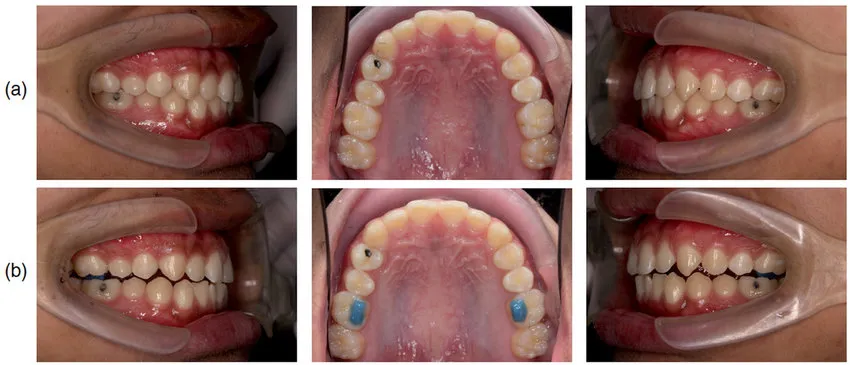

또한 어태치먼트라고 불리는 작은 돌기를 치아 표면에 부착하여 장치의 유지력을 높이고, 특정 방향으로의 치아 이동을 돕습니다.

✅바이트 램프

기존 철사 장치로 과개교합을 치료할 때는 바이트 블럭이라는 재료를 사용했습니다.

이것은 파란색 레진 재질로, 주로 어금니 교합면에 올려 사용합니다.

위아래 치아가 깊게 물리는 것을 막아 교합을 띄워주는 역할을 합니다.

그러나 환자 입장에서는 이 돌출된 부분 때문에 음식을 씹기가 상당히 불편했습니다.

어금니가 제대로 맞물리지 않으니 저작 효율이 떨어지고, 음식을 잘게 부수기 어려웠습니다.

적응하는 데 수주에서 수개월이 걸리는 경우도 있었습니다.

중랑구 교정치과 인비절라인 에서는 바이트 램프라는 구조물이 같은 기능을 수행합니다.

이 장치는 투명교정 장치 내부에 양형으로 튀어나온 형태로 설계됩니다.

위치는 주로 윗니 앞니 안쪽 부분에 해당하는데, 아랫니가 이 돌출 부분에 먼저 닿으면서 윗니 앞니를 뿌리 방향으로 밀어 넣는 힘이 작용합니다.

이러한 치아 이동을 함입(intrusion)이라고 하며, 깊게 물리는 교합을 개선하는 핵심 원리입니다.

어금니의 위치를 조정하여 전체적인 교합 높이를 맞추는 작업도 함께 진행됩니다.

무엇보다 중요한 것은 식사할 때 장치를 뺄 수 있다는 점입니다.

바이트 블럭을 부착한 상태로 식사해야 했던 기존 방식과 달리, 저작에 전혀 불편함이 없습니다.

장치를 빼면 평소와 동일하게 음식을 씹을 수 있어 일상생활의 편의성이 크게 향상됩니다. (식후에는 양치를 하고 장치를 다시 착용할것을 권장드립니다)